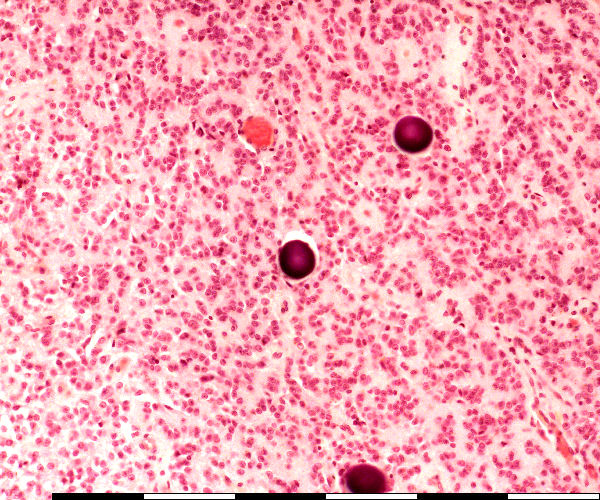

Pineal gland: High magnification

Breinsand / Brein sand

Pinosiete / Pinealocytes

Bloedvate / Blood vessels

Glia selle/ Interstitial (glial) cells

Fibroblaste / Fibroblast

Selle in die pineaalklier / Cells in the pineal gland